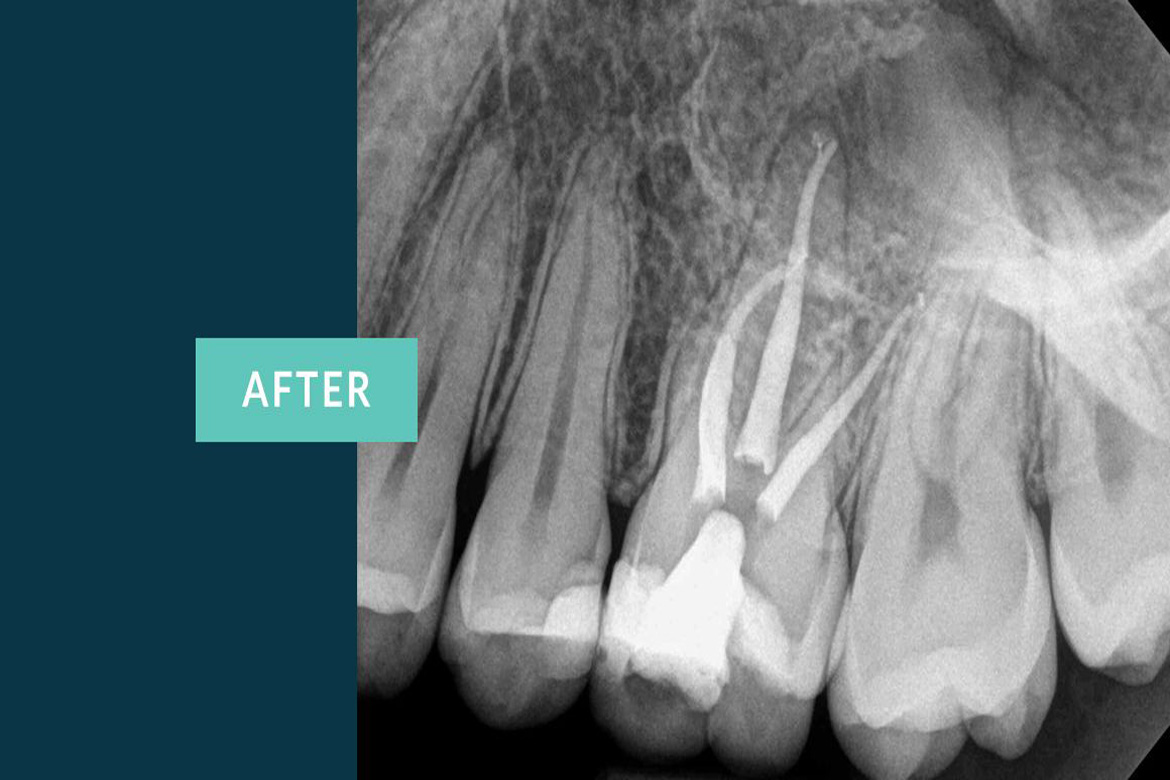

The primary intent of Root canal treatment is to remove the diseased pulp ,clean ,cleanse ,irrigate shape and then fill the canals of the tooth.

Root canal is filled completely with an inert material called Guttaperchathis is to advocate periradicular healing and prevent reinfection of the tooth there by preserving the natural tooth thus maintaining the balance in the oral cavity.

Thanks to the advanced technology which introduced Nickel-Titanium rotary instuments,apexlocators,ultrasonics,lasers and microscopic endodontics which maked the work of a Dentist easy and hasslefree . These latest inventions helped the dentists achieve dental procedures more precisely than before.